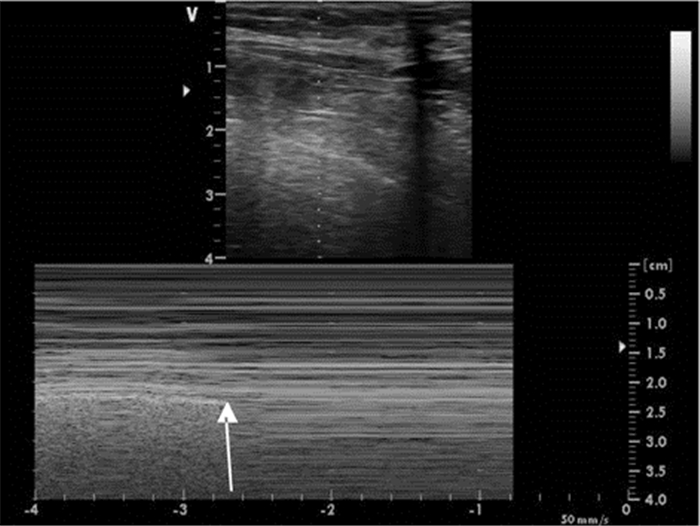

超声检查IVC内径及其随呼吸的变异率不但能提供患者容量状态的信息,有时还能评估液体反应性(图 19、20)。ASE(美国心超协会)指南的建议:用力吸气时,IVC直径≤2.1 cm伴随呼吸变异率>50%,对应于中心静脉压(CVP)值3 mmHg(0~5 mmHg,1 mmHg=0.133 kPa),IVC直径>2.1 cm伴随呼吸变异率<50%,对应的CVP值为15 mmHg(10~20 mmHg);如IVC直径≤2.1 cm伴随呼吸变异率<50%或IVC直径>2.1 cm伴随呼吸变异率>50%,提示对应的CVP值可能为8 mmHg(5~10 mmHg),此时应考虑采用其他指标来估测CVP[1]。其他文献报道数值略有不同,平静呼吸时,IVC直径≤2 cm伴随呼吸变异率>50%,对应于CVP值≤10 mmHg,可见于低血容量和分布性休克患者;IVC直径>2 cm伴随呼吸变异率<50%,对应的CVP值大于10 mmHg,可见于心源性和梗阻性休克患者[2]。

| 图 20 M超显示IVC随呼吸直径发生变化 |

但IVC的超声成像有时比较困难,特别是肥胖、腹胀和肠胀气明显的患者;而且IVC大小还受机械通气患者呼气末正压(PEEP)的影响,用来估计CVP有一定的缺陷[3]。在完全控制通气模式下(无自主呼吸触发)时,吸气相IVC扩张超过12%~18%,可较好的预测容量反应性。IVC管径随着PEEP水平的增加而升高,呼吸变异率随PEEP的增加而变小,但目前PEEP对IVC容量评估的影响尚无定论,有待进一步临床研究。